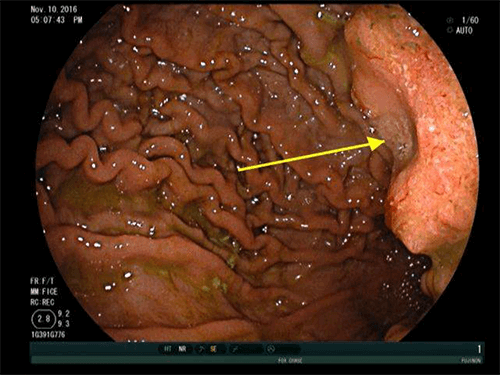

We report a case of colorectal metastases to the gastric mucosa approximately 3 years after resection of the primary tumor. Our patient was a 71-year-old male with a history of stage IIIB, pT3N1cM0 moderately differentiated adenocarcinoma of the transverse colon status post laparoscopic transverse colectomy on January 28, 2013, followed by adjuvant FOLFOX administered between March 2013 and August 2013. On surveillance imaging in March 2014, he was found to have a solitary FDG-avid left hepatic lobe lesion confirmed to be a hepatic colorectal metastasis on US-guided FNA. He underwent partial left hepatic lobectomy on April 2014. He subsequently received continued cancer surveillance with periodic imaging, colonoscopy, and serum carcinoembryonic antigen (CEA) levels with no evidence of disease. In particular, his CEA prior to the colectomy was 0.8 ng/ml and prior to his gastrectomy was 1.4ng/ml, therefore his tumor was not a CEA producer. In October 2016, he presented with fatigue, 16 pound weight loss, shortness of breath, and anemia. As before, his CEA remained within normal limits. He underwent an EGD which revealed a 3 cm, raised, fungating mass with a central depression in the gastric body along the lesser curvature just above the incisura (Figure 1). Subsequent EUS was consistent with a 27 mm, uT2-3N0 tumor (Figure 2).

Figure 1. EGD revealed a 3 cm, raised, fungating, mass with central depression (“bull’s eye sign”, yellow arrow) in the gastric body along the lesser curvature just above the incisura.

At EGD, gastric mucosal metastases can usually be categorized into one of three categories based on their endoscopic features: non-ulcerated masses, submucosal masses with ulceration at their apex, or multiple nodules of varying sizes with ulceration.7,8 Some reports have described a characteristic “bull’s eye sign”, or a raised lesion with central depression.9,10 In a series from the National Cancer Center Hospital in Tokyo composed of 54 patients with gastric mucosal metastases and 347 autopsy cases, the majority of tumors were solitary (65 percent) versus multiple (35 percent).1 In addition, the majority of lesions were located in the middle or upper thirds of the stomach.1 Our patient had a solitary, fungating mass with a central depression located along the lesser curve in the mid-body. Lesions can also appear as polypoid masses ulcers, ulcerated protruding lesions, or thickening of the gastric wall.7,11 Of note, the primary tumor type may dictate the endoscopic features of the gastric mucosal metastasis. For example, gastric mucosal metastases from melanoma may appear as melanotic nodules or as masses with necrosis and melanosis on EGD.12